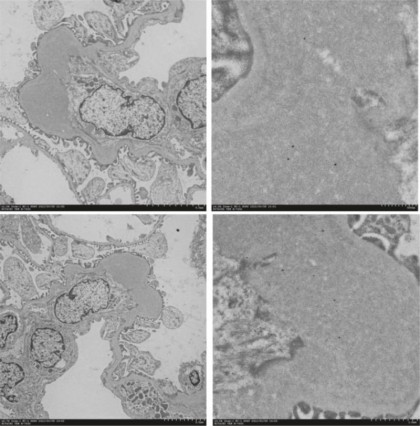

Rezultatele au arătat că hematuria era semnificativ mai mare la grupurile care au primit tulpina Cnm-pozitivă, tulpina complementară și rCnm, comparativ cu grupurile de control negative. Acest fapt sugerează că proteina Cnm sau S. mutans care exprimă Cnm pot induce hematurie în stadiile incipiente ale IgAN. Nu au fost observate schimbări semnificative în proteinurie sau în funcția renală între grupurile studiate.Analiza histologică a secțiunilor de țesut renal a relevat o proliferare crescută a celulelor mezangiale și a matricei mezangiale în grupurile Cnm-pozitive și rCnm, în comparație cu grupurile Cnm-negative. De asemenea, depozite mai mari de IgA, complement C3 și IgG au fost observate în regiunea mezangială a glomerulilor la șobolanii injectați cu tulpina Cnm-pozitivă. Prezența proteinei Cnm în regiunea mezangială la animalele injectate cu rCnm indică faptul că proteina însăși poate avea un rol patogen în dezvoltarea IgAN.

foto: Dr. Shuhei Naka, Okayama University